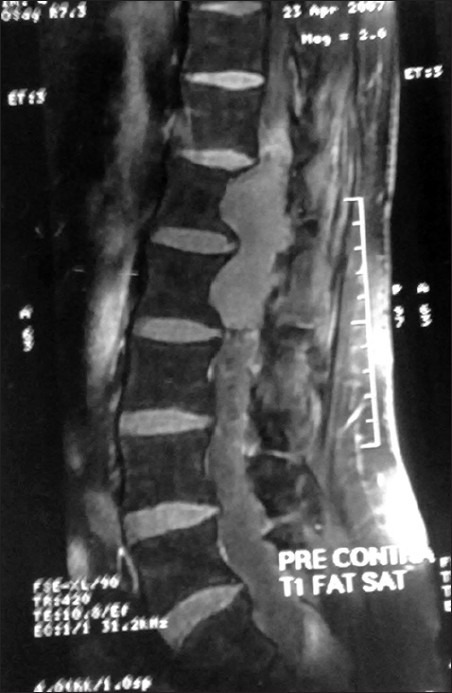

脊髓空洞综合征(Conus-cauda syndrome)是由于脊髓下端和神经根束受累所致。常见的病因是外伤、椎管狭窄、脊髓肿瘤、炎症和感染性疾病,但副神经节瘤是一种罕见病因。这些肿瘤很少具有分泌儿茶酚胺的功能。据我们所知,迄今为止只有五例功能性脊髓副神经节瘤的病例报告。我们报告了一名 50 岁的男性高血压患者,其病变呈分叶状,从 D12 下缘延伸至 L2,术前影像学检查报告为上皮瘤。该病变在术后被证实为功能性副神经节瘤,而患者因该病变引起的严重并发症而死亡,因此凸显了术前诊断和处理的重要性。总之,锥尾功能性副神经节瘤非常罕见。从内科和外科治疗的角度来看,在术前对其进行诊断至关重要。在手术过程中,应非常小心地处理这些肿瘤,以避免儿茶酚胺进入血液。这些肿瘤在围手术期需要麻醉师和内分泌专家的协助。

Conus-cauda syndrome is caused due to involvement of the lower end of the spinal cord and arising bunch of nerve roots. It is caused commonly due to traumatic injury, spinal stenosis, spinal tumors, inflammatory, and infectious conditions, but paraganglioma is a rare cause. These tumors are rarely functional and secrete catecholamine. Till now only five case reports of functional spinal paragangliomas are available to the best of our knowledge. We report a 50-year-old hypertensive male patient with a lobulated lesion extending from lower border of D12 to L2, which was reported as ependymoma on imaging studies done preoperatively. This lesion was confirmed to be a functional paraganglioma postoperatively after the patient died because of its furious complication, thus highlighting the importance of its preoperative diagnosis and management. In conclusion conus-cauda functional paragangliomas are very rare entity. Diagnosing them in preoperative condition is critical from the therapeutic point of view, both medical and surgical. During surgery these tumors should be handled very gently to avoid spillage of catecholamines into blood. These tumors require assistance of expert anesthetist and endocrinologist in the perioperative period.